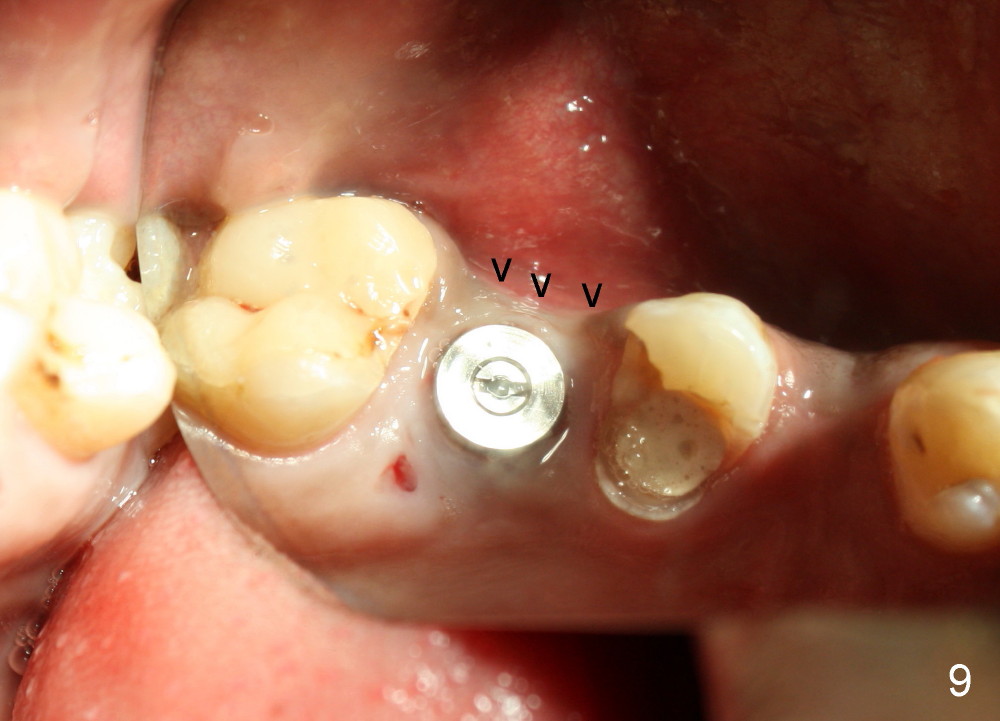

The socket looks empty two months post-extraction (Fig.4 S). Bone appears to re-grow in the socket 9 months after extraction (Fig.5 S), but the buccal plate is severely atrophic and concave (Fig.6 arrowheads). When an incision is made, the socket feels soft. Osteotomy is created by bone expansion (round tapered osteotomes (RT) 2,3,4 mm). Drilling is done once, using 3.5x17 mm tapered drill when the larger RTs meet resistance near the sinus floor. Tapered taps are used to continue to expand the osteotomy (4.5 (Fig.7), 5.0 and 6.0x20 at the depth of 17 mm). Finally 6.0x17 mm implant is placed with insertion torque more than 60 Ncm (Fig.8). The buccal plate is less concave with bone expansion and implantation (Fig.9 arrowheads). Without immediate implant, bone resorbs quick, which makes delayed implantation difficult.